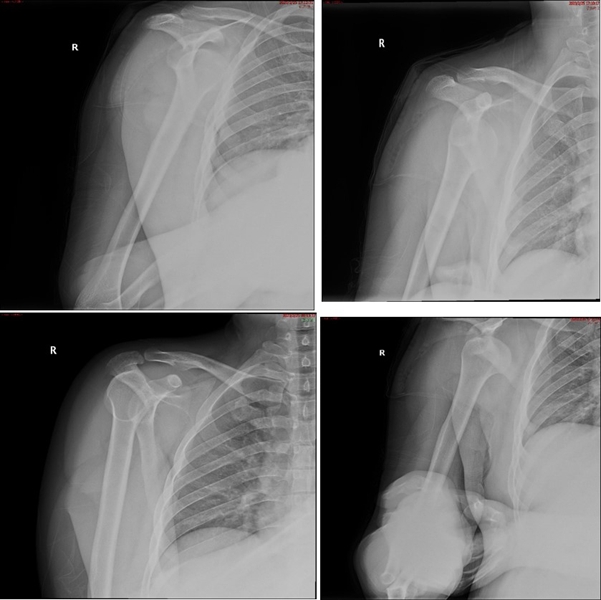

Case1:影像学评估病例,19岁,打篮球摔伤脱位。

图23 首次脱位

图24 打球再次受伤,复发脱位

双侧CT三维扫描显示:健侧肩胛盂宽度D=25.9,患侧D=23.9,患侧肩胛盂骨性缺损d=6.2,骨性盂唇缺损面积d/D为23.9%(<25%)。肩胛盂轨迹GT(83%D-d)为15.3mm。

图28双侧CT三维扫描

图29 Hill-Sachs间隙为13.8mm(<15.3mm)

图30 评估结果

评估报告提示:右肩胛骨关节盂前下缘撕脱骨折,符合骨性bankart损伤。右肱骨头后上缘凹陷骨折,符合Hill-Sachs损伤。Hill-Sachs间隙为13.8mm(<15.3mm),为轨迹内肩关节前脱位。